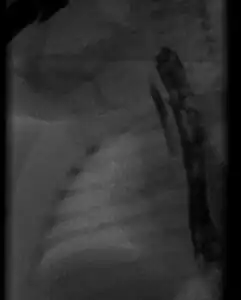

TEF should be suspected once the baby fails to swallow after their first feeding during the first day of life. Esophageal atresia can be diagnosed by Ryle nasogastric tube; if the Ryle fails to pass into the stomach, then this indicates esophageal atresia and loss of communication between stomach and esophagus. TEF may be diagnosed by MRI which clarifies the atretic esophagus (if presents) and TEF, as well as its location and anatomy. Gastrograffin contrast swallow should not be used if TEF is suspected, due to its high risk of allergy and severe intractable chest infection.